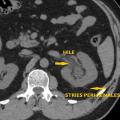

• en cas de calcul, de déterminer sa taille et sa localisation (impact pronostique important pour l’expul­sion spontanée ou le choix d’une technique interventionnelle) et leur nombre en cas de calculs multiples (fig. 1 et 2).

La sensibilité de l’échographie ou de l’abdomen sans préparation (ASP) isolément pour le diagnostic de calcul (respectivement de 80 et 90 %) ne les font recommander qu’en association (fig. 3). Pour l’imagerie initiale, cette association a été supplantée par le scanner abdominal compte tenu de sa rapidité de réalisation, pour un surcoût marginal, et de sa grande efficacité pour le diagnostic positif et différentiel. Le scanner a, en outre, un impact pronostique important pour l’expulsion spontanée (en fonction de la taille et de la localisation au diag­nostic) mais aussi le choix du traitement, la sensibilité aux ondes de choc étant à peu près corrélée à la densité tomodensitométrique.